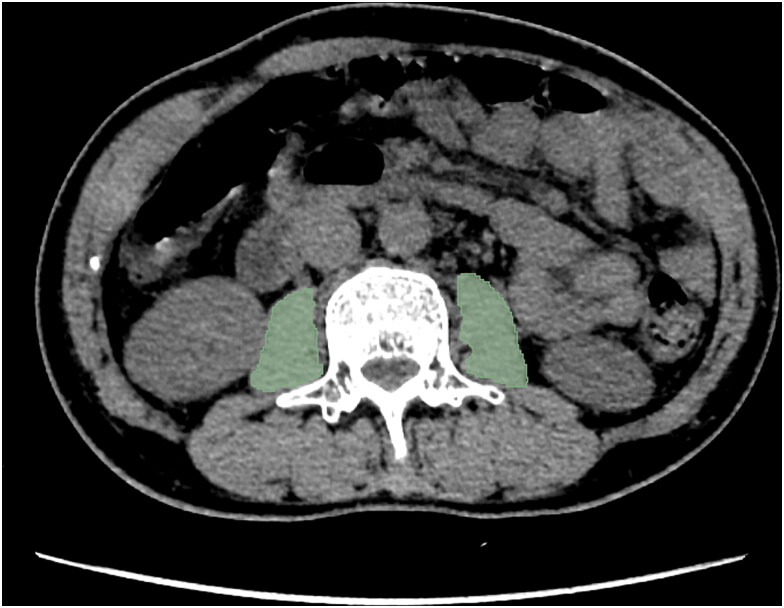

Methods: In this retrospective study, patients with CD from two institutions were recruited between January 2010 and January 2023, following stringent inclusion and exclusion criteria. Regions of interest were delineated using 3D Slicer software, and radiomics features were extracted with the Pyradiomics package in Python. Z score standardization and independent sample t test were applied to identify optimal predictive features, which were then utilized in seven ML algorithms for training and validation. Model performance was assessed through receiver-operating characteristic curves, precision-recall curves, and calibration curve analyses, evaluating accuracy and clinical applicability. Binary logistic regression was employed to identify predictors of IFX treatment response.

背景:克罗恩病(CD)是一种慢性炎症性肠病,常用英夫利昔单抗(IFX)治疗。然而,目前还没有临床适用的模型来预测CD患者对IFX治疗的反应。考虑到肌肉减少症与IFX治疗结果之间的强烈关联,本研究开发了基于计算机断层扫描放射学的机器学习(ML)模型,利用腰肌体积作为骨骼肌质量的代理,来预测CD患者对IFX治疗的反应。方法:在这项回顾性研究中,遵循严格的纳入和排除标准,从2010年1月至2023年1月从两个机构招募了CD患者。使用3D切片器软件描绘感兴趣的区域,使用Python中的Pyradiomics包提取放射组学特征。采用Z评分标准化和独立样本t检验来识别最佳预测特征,然后将其用于7种ML算法的训练和验证。通过接受者-工作特征曲线、精密度-召回率曲线和校准曲线分析来评估模型的性能,评估模型的准确性和临床适用性。采用二元逻辑回归来确定IFX治疗反应的预测因素。结果:共纳入134例患者,分为训练组(n = 84)和验证组(n = 50)。选择20个不同的放射组学特征整合到ML模型中。所有模型在验证队列中均表现出较强的预测性能,曲线下平均面积为0.849。极端梯度增强算法优于其他算法,实现了0.910的曲线下面积。结论:基于腰肌计算机断层放射学的ML模型可以有效预测CD患者对IFX治疗的反应,其中eXtreme Gradient Boosting模型表现出更好的效果。